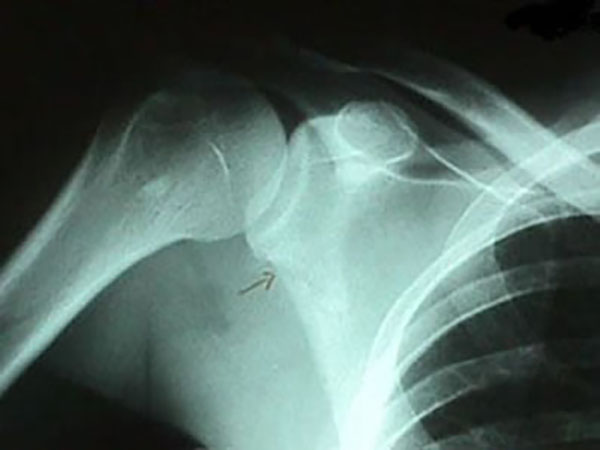

肩甲骨関節窩部骨折

上腕骨(二の腕の骨)と肩関節をつくる部分の骨折です。上図の赤丸部分です。

肩外側から引っ張られる力が加わった時に生じやすく、肩関節脱臼を合併することが多いです。

関節窩部骨折は関節内骨折なので、肩関節の可動域制限が残る可能性があります。